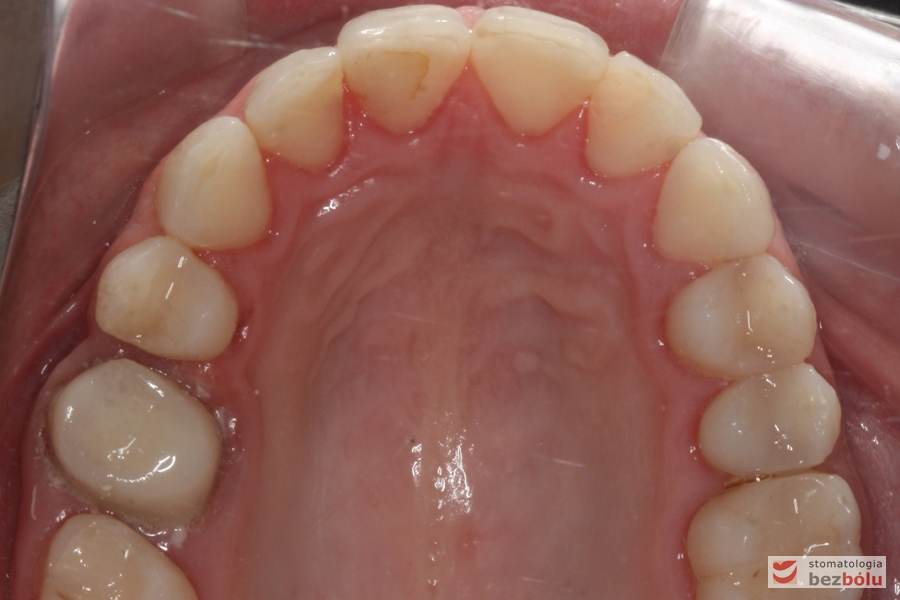

Zwężenie szczęki - brak "piątki" po stronie prawej, mezjalizacja sektora bocznego na skutek stłoczeń trzeciorzędowych

Zwężenie szczęki – brak „piątki” po stronie prawej, mezjalizacja sektora bocznego na skutek stłoczeń trzeciorzędowych